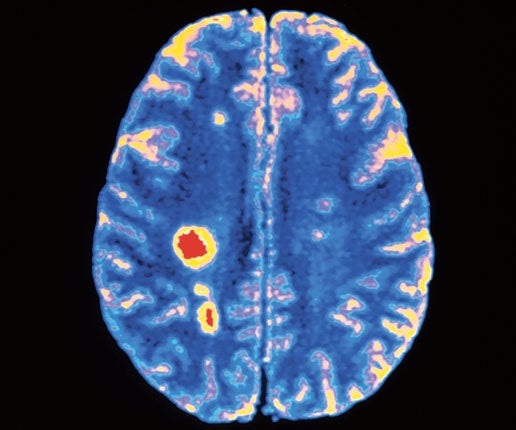

Los investigadores Khanitin Jornkokgoud, Teresa Baggio, Md Faysal, Richard Bakiaj y Peera Wongupparaj dijeron en su documento publicado en la revista Neuroscience News Communications: “Los resultados mostraron que un circuito que incluía las circunvoluciones frontales lateral y media, la circunvolución angular, el opérculo rolándico y la circunvolución de Heschl predijo con éxito los rasgos de personalidad narcisista”.

Los autores detallaron que “los rasgos narcisistas fueron predichos por rasgos de personalidad normales (apertura, amabilidad, escrupulosidad) y anormales (límite, antisocial, inseguro, adicto, negativista, maquiavelismo)”.

Este estudio es el primero en predecir rasgos de personalidad narcisista mediante un enfoque de aprendizaje automático supervisado. Como tal, estos resultados pueden ampliar la posibilidad de derivar rasgos de personalidad a partir de características neuronales y psicológicas.